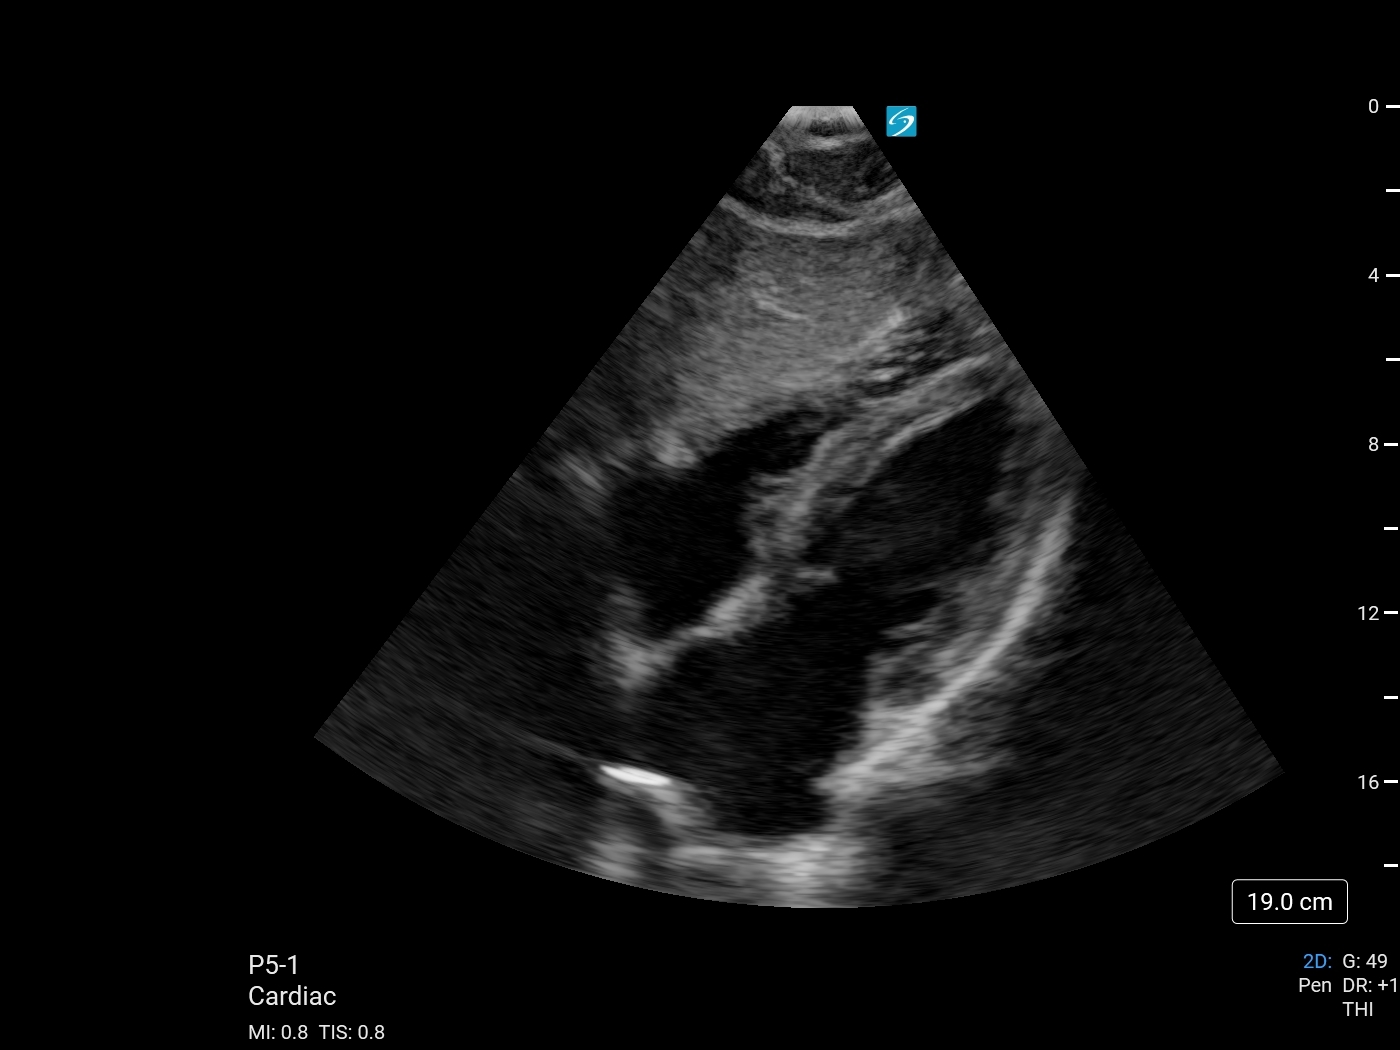

Bild 2: Herz, subkostaler 4-Kammerblick (mit blauem Punkt)